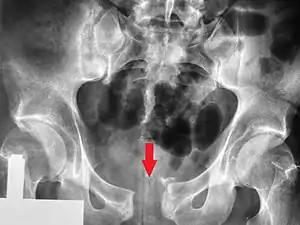

![]() | |

| A pelvic X-ray showing an open book fracture | |

Open book fracture

One specific kind of pelvic fracture is known as an 'open book' fracture. This is often the result of a heavy impact to the groin (pubis), a common motorcycling accident injury. In this kind of injury, the left and right halves of the pelvis are separated at front and rear, the front opening more than the rear, i.e. like an open book that falls to the ground and splits in the middle. Depending on the severity, this may require surgical reconstruction before rehabilitation.[11] Forces from an anterior or posterior direction, like head-on car accidents, usually cause external rotation of the hemipelvis, an “open-book” injury. Open fractures have an increased risk of infection and hemorrhaging from vessel injury, leading to higher mortality.[12]